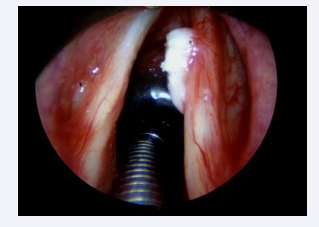

This prevalence is justified due to the surgeon’s special attention during the trans-operative period, and the following aspects were observed: the leukoplakia may be microscopic, it may be located throughout the glottis, especially at the vocal fold level, it may be associated to the initial surgical lesion, it may be contralateral to it, it may be located in the epithelium of this lesion or it may also be subglottic. Intraoperative staging with microscopy, palpation maneuvers and the use of rigid endoscopes angled at 30, 70 and 120 degrees favor the detection of leukoplastic lesions [Figures 2-5].

Leukoplakia with variation in location and quantity

Figure 4: Leukoplakia with variation in location and quantity